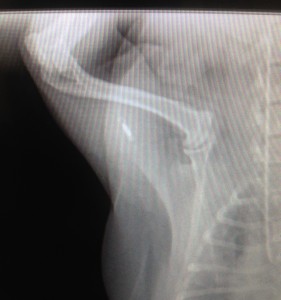

Another little known fact is that microchips can occasionally migrate from their correct position between your pet’s shoulder blades. Chips have been known to migrate to other parts of a pet’s body, and if a vet or shelter performs a quick scan in the usual chip location, they could miss your pet’s chip. An easy way to make sure your chip has stayed where it should is to ask your pet’s veterinarian to scan your pet once a year for a chip, and make sure that the correct information pops up on the scanner. If the microchip cannot be detected, a new microchip may be needed.

This microchip has migrated from between the shoulders to the pet’s shoulder blade. Photo credit: Eagle View Vet Hospital.